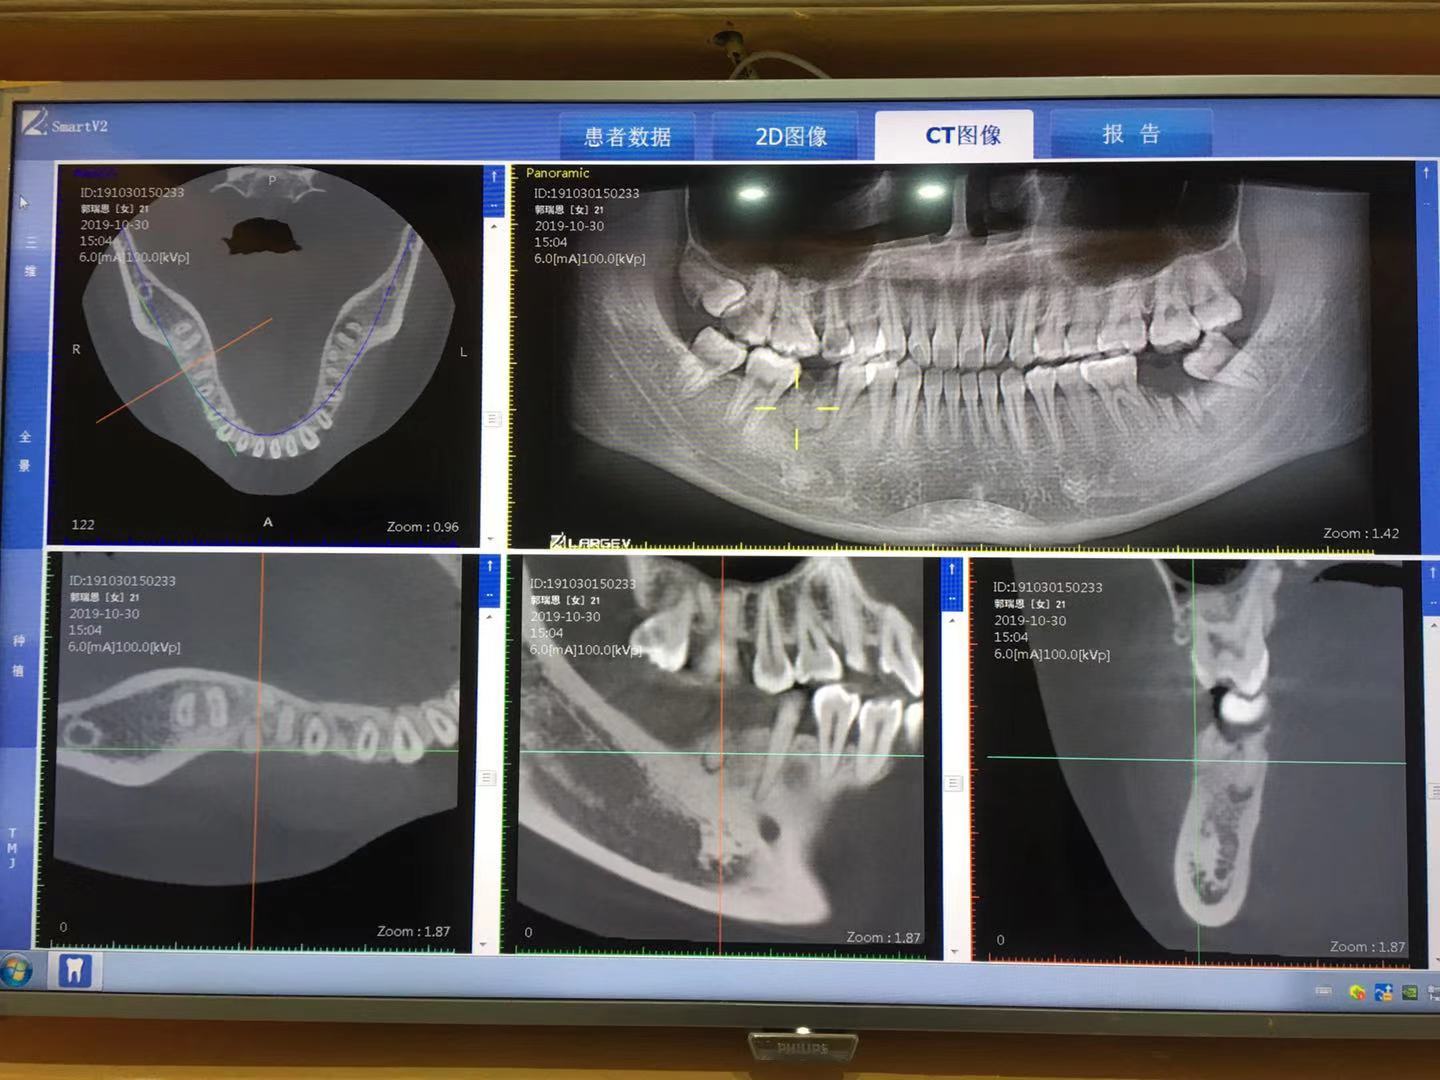

针对 21 岁患者下颌阻生智齿伴牙体缺损,经 CBCT 精准评估,行微创拔除 + 同期种植修复,精准把控骨条件,为后续功能与美学重建奠定基础。